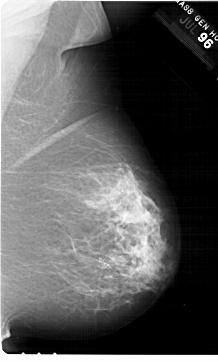

A_1774_1.LEFT_CC

LEFT_CC LINES 6871 PIXELS_PER_LINE 4651 BITS_PER_PIXEL 12 RESOLUTION 43.5 OVERLAY